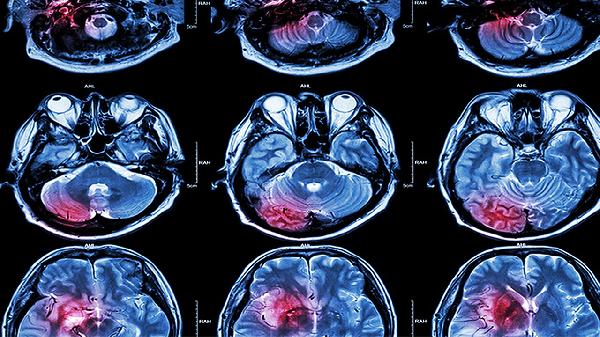

脑外伤后头痛可通过药物镇痛、物理治疗、心理干预、生活方式调整及手术治疗等方式缓解。脑外伤后头痛通常由颅内压变化、神经损伤、血管痉挛、炎症反应及心理因素等原因引起。

对于硬膜下血肿或严重脑挫裂伤引起的顽固性头痛,需行血肿清除术或去骨瓣减压术。颅骨缺损导致的体位性头痛可通过颅骨修补术改善。所有手术方案需经神经外科评估后实施。